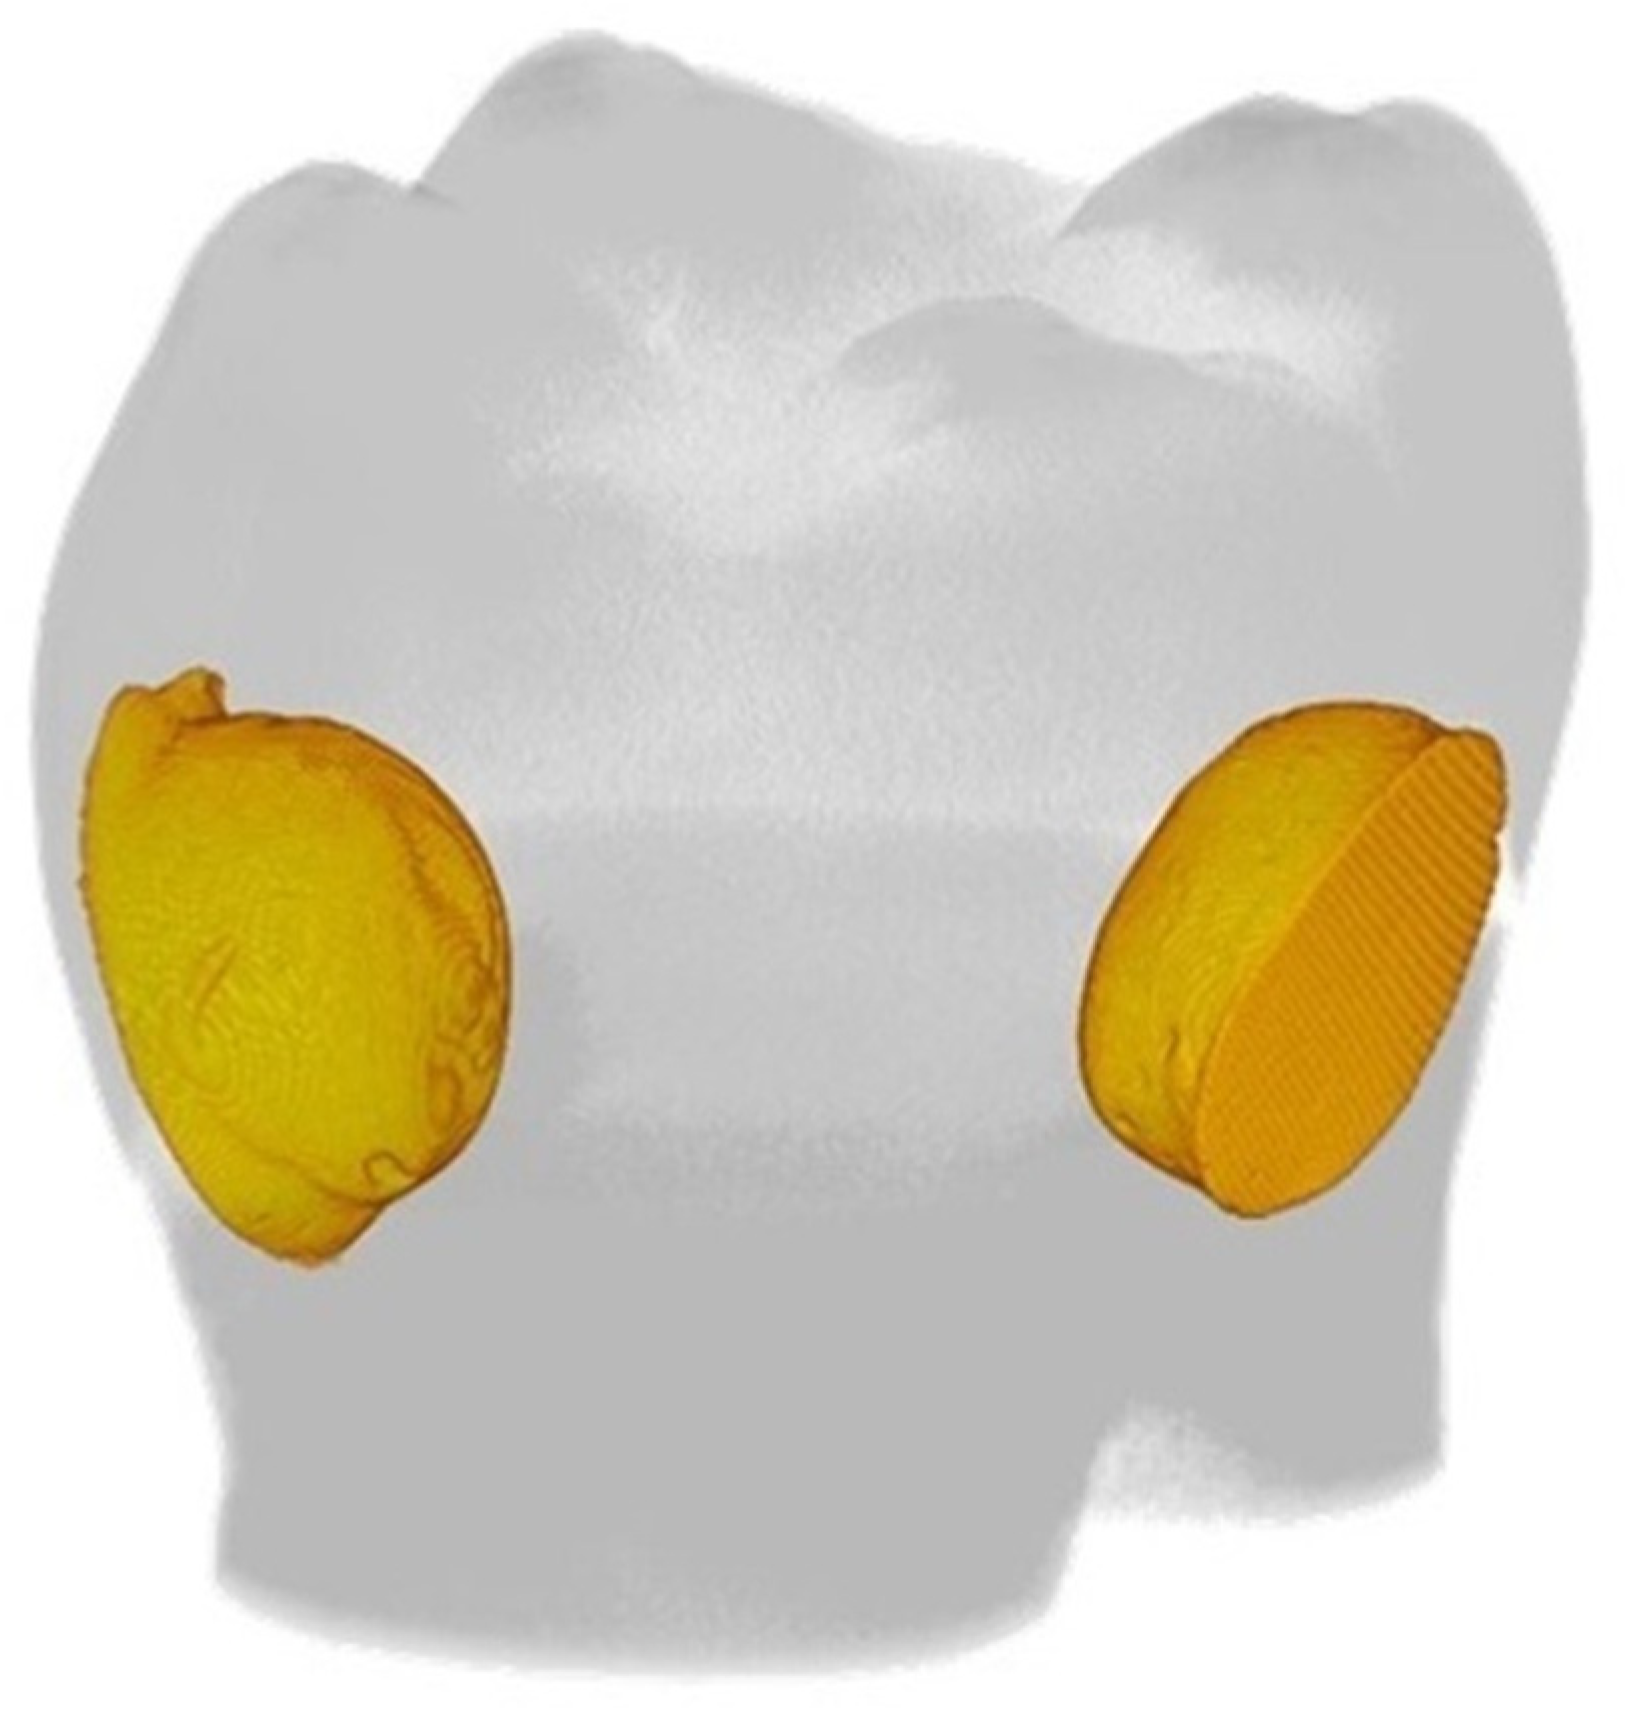

3. Results

4.1. Thermomechanical Loading (TML) and Water Degradation Analysis

4.2. Micro-Computed Tomography (µCT) Analysis

4.3. Gap Volume to Filling Volume (GV/FV) and Gap Volume to Cavity Volume (GV/CV) Ratios